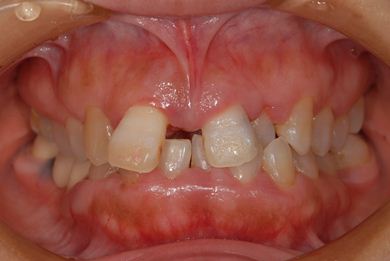

| 性別/年齢 | 女性 / 52歳 | ||||||||||||||||||||||||||||||||

| 主訴 | 歯周病で歯の位置がずれてしまった。 | ||||||||||||||||||||||||||||||||

| 治療内容 | インプラント2本(抜歯即日スピードインプラント)、メタルボンドセラミッククラウン4本 | ||||||||||||||||||||||||||||||||